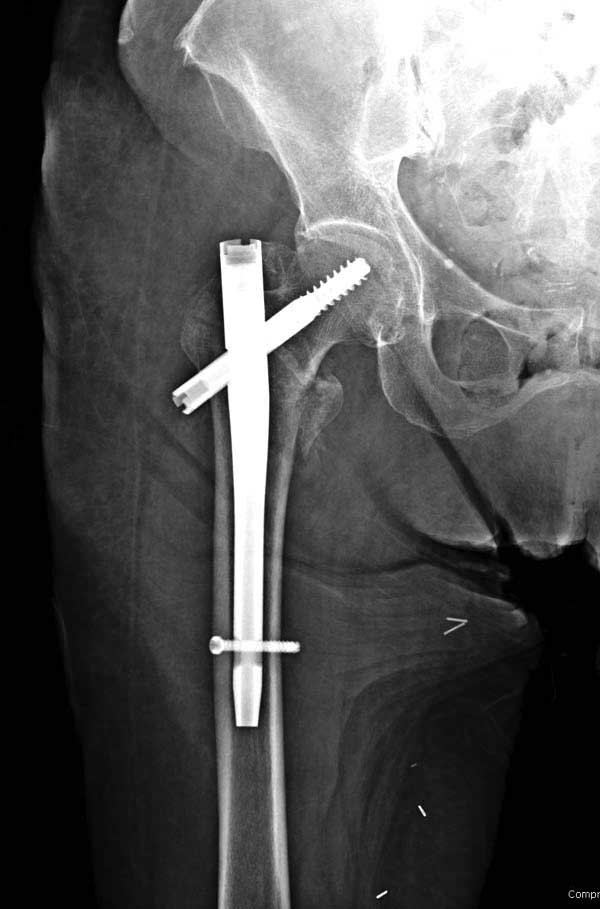

Прилагаю снимок сделанный еще в стационаре через 2 недели после операции.

Сеньоры-пэры ревизировали гвоздем, шуруп поставили по той же дорожке, только поглубже. Да еще и bone graft не пожалели. "Результат" уже был через 2 дня.

Если сохранять головку - думаю надо было в валгусе фиксировать перелом гвоздем, или DCS, т.к. все-равно разрезали, чтоб достать DHS.

Первые снимки показывают технические погрешности установки DHS. Не была достигнута репозиция, конечность в флексии и шейка в ротации. Сегодня все меньше обращают внимание на параметры для оценки репозиции (S контуры Lowell в обеих проекциях и Garden Alignment Index, в норме 155 и 180 градусов), хотя такие простые тесты помогли бы дорепонировать смещение. Винт находится сзади в головке, что при нагрузке поменяет вектор и вместо компрессии в линии перелома срежет головку-Cut Out!

В зависимости от дистанции линии перелома и латерального кортекса надо использовать разной длины barrel, т.е. конец баррели не должен доходить до пределов перелома. Здесь конец длинного ствола упирается в медиальный фрагмент, что мешает созданию компрессии, а более короткий barrel создал бы запас для компрессии. В боковой пластине вместо 4х можно было ограничится двумя шурупами, потому что головка шурупа в 4.5 мм выдерживает давление до 350 кг.

Вторая операция- это фаза сохранения головки бедра. Желательно приложить все усилия и сохранить головку, но, как видно, “фиаско” продолжается. Здесь вместо нейтрализации сил между медиальной и латеральными сторонами была попытка удержать варус. Варус не удержать ни деротационными шурупами о котором говорили и не костными стружками вбитые в шейку, потому что вся нагрузка упирается в головку.

Как отметил Евгений, 95 degree Blade Plate Fixed Angle device расчитана на восстановление взаимоотношении между головкой и диафизом, а все остальные фиксаторы (Gamma, Afifuxus и др.) работают за счет нагрузки в верхнем полюсе головки. Верхний полюс успели разрушить, и в головке единственное место, который смог бы удержать широкий клинок конструкции, это медиально-низкий сегмент. После установки клинка засчет дистракции можно удлинить конечность на 15мм, а добавленный в дефект ауто-графт закончил бы дело.